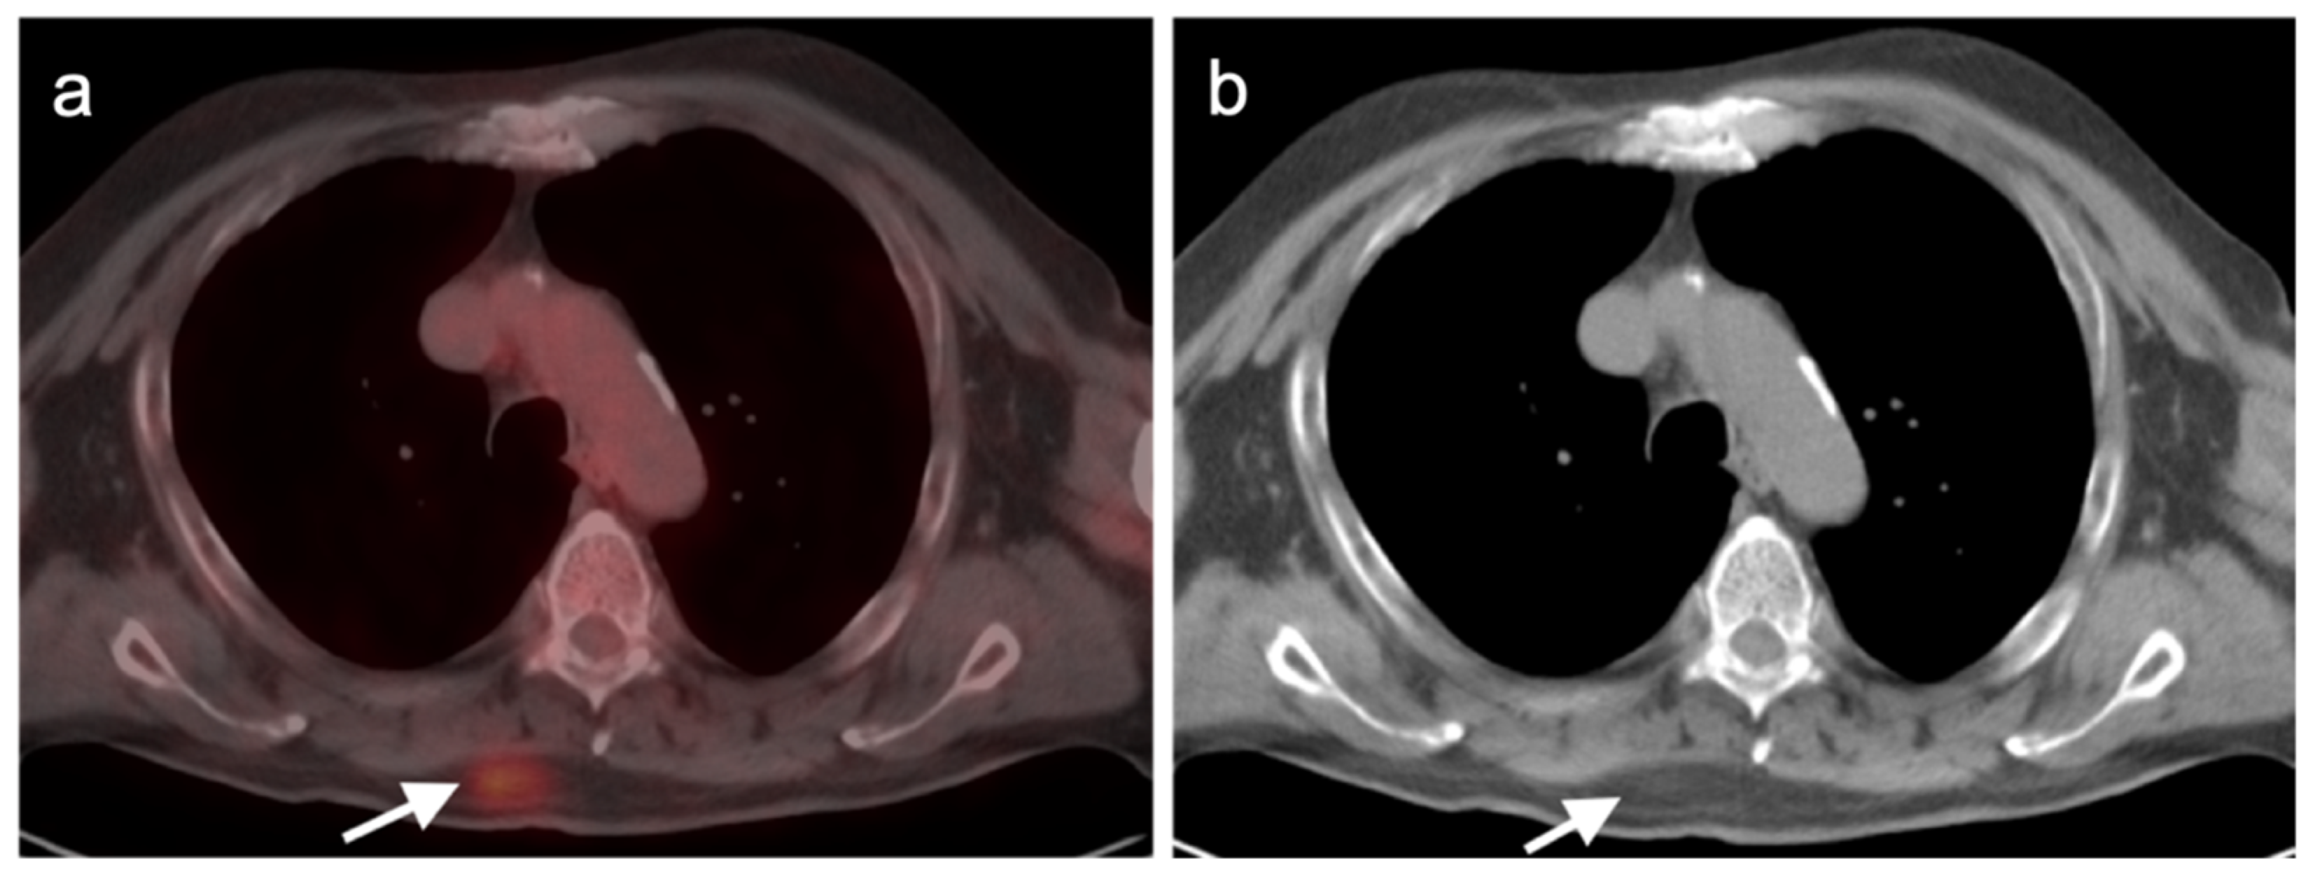

4.4. Bronchial Carcinoid

- Kayani, I.; Conry, B.G.; Groves, A.M.; Win, T.; Dickson, J.; Caplin, M.; Bomanji, J.B. A Comparison of 68Ga-DOTATATE and 18F-FDG PET/CT in Pulmonary Neuroendocrine Tumors. J. Nucl. Med. 2009, 50, 1927–1932. [Google Scholar] [CrossRef] [Green Version]

- Zidan, L.; Iravani, A.; Kong, G.; Akhurst, T.; Michael, M.; Hicks, R.J. Theranostic implications of molecular imaging phenotype of well-differentiated pulmonary carcinoid based on 68Ga-DOTATATE PET/CT and 18F-FDG PET/CT. Eur. J. Pediatr. 2020, 48, 204–216. [Google Scholar] [CrossRef]

- Tatci, E.; Ozmen, O.; Gokcek, A.; Biner, I.U.; Ozaydin, E.; Kaya, S.; Arslan, N. 18F-FDG PET/CT rarely provides additional information other than primary tumor detection in patients with pulmonary carcinoid tumors. Ann. Thorac. Med. 2014, 9, 227–231. [Google Scholar] [CrossRef]